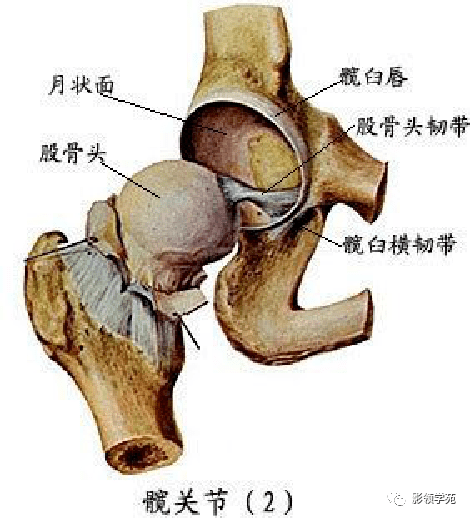

关节与韧带系统

韧带系统

关节与韧带系统

韧带系统